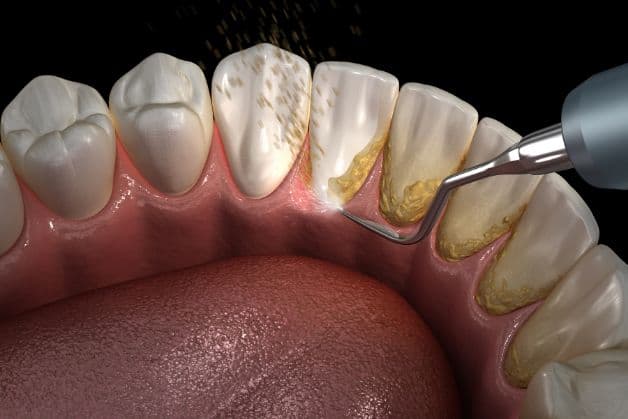

Lấy sạch cao răng là một phương pháp loại bỏ ổ viêm nhiễm.

Bác sĩ có thể thực hiện điều trị bệnh, loại bỏ ổ viêm nhiễm bằng các biện pháp:

– Tiến hành làm sạch chân răng, lấy vôi răng